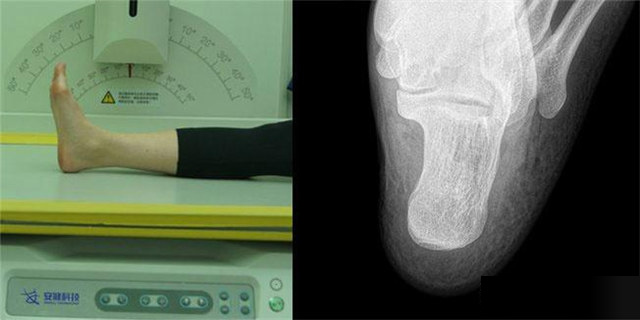

下肢:脛腓骨、踝、足脛腓骨長骨檢查需要包括--側(cè)的關(guān)節(jié)踝關(guān)節(jié)常規(guī)正+外側(cè)位,特殊時(shí)可選內(nèi)斜位足常規(guī)前后正位+內(nèi)斜位,外傷鑒定等情況,需要負(fù)重的水平側(cè)位(包括足尖和足跟)跟骨側(cè)位+軸位